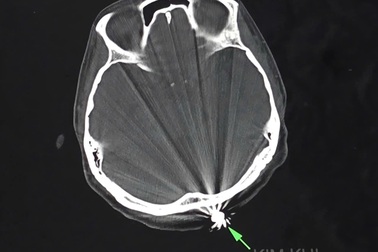

Người phụ nữ đang làm vườn bất ngờ bị trúng đạnNgười phụ nữ 40 tuổi ở Cần Thơ đang làm vườn bất ngờ bị một vật cứng dạng tròn bay đến găm vào vùng chẩm, chảy máu nhiều. Qua phẫu thuật, các bác sĩ kết luận nạn nhân bị đầu đạn xuyên qua da đầu.

Tìm được thủ phạm dùng súng bắn chim làm người phụ nữ bị trúng đạnSự dùng súng hơi bắn chim, cách chỗ nạn nhân bị bắn trúng khoảng 100m. Anh ta khai, trong lúc săn bắn không biết đạn găm vào đầu hàng xóm.